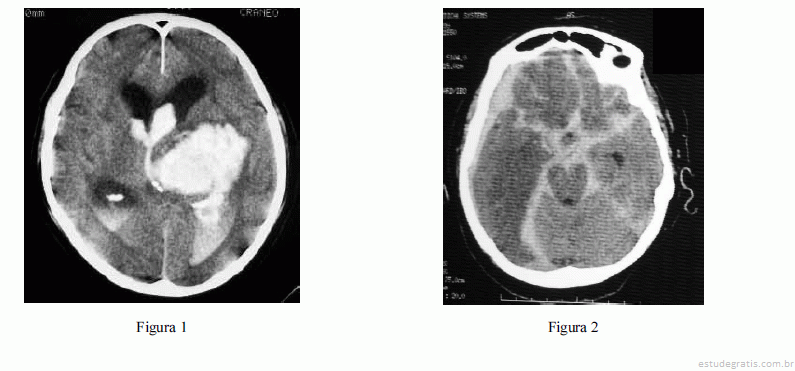

Com relação às figuras 1 e 2 acima, que mostram os exames de imagem de dois pacientes distintos, julgue os itens que se seguem.

Nos casos retratados nas figuras 1 e 2, o traçado de onda de pressão intracraniana desses pacientes deverá mostrar elastância cerebral aumentada.Comentários